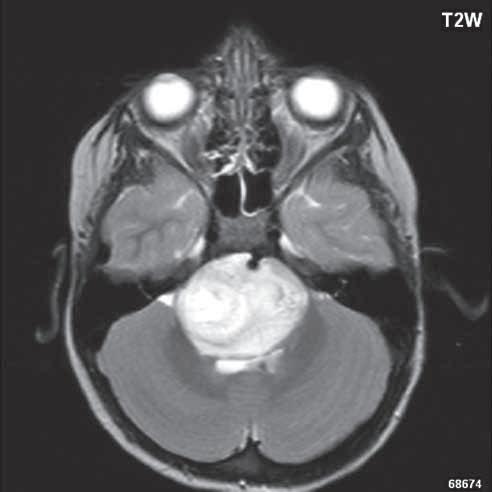

Zobrazení

D-W malformace je charakterizována hypoplazií vermis mozečku, rozšířením IV. mozkové komory, která se často cysticky vyklenuje dorzálně a může imitovat arachnoidální cystu, rozšířením zadní jámy lební a vysokým úponem tentoria s confluens sinum nad lambdovým švem. Okcipitální kost může být vlivem tlakových změn remodelována, existují i případy s porušením její kontinuity a encefalokélou. Hydrocefalus pozorujeme v 80 %, častá je přítomnost dysgeneze corpus callosum, schizencefalie.

Obr. I.1.8a Dandy-Walkerova malformace, rozšířená IV komora (tvar klíčové dírky)

Obr. I.1.8b Dandy-Walkerova malformace, rozšířená IV komora široce komunikující s cisterna magna, hypotrofie mozečku (snímky zapůjčeny z archivu prim doc MUDr M Mechla, Ph D, MBA)

Obr. I.1.8c Dandy-Walkerova malformace, rozšířená IV komora široce komunikující s cisterna magna, hypotrofie mozečku (snímky zapůjčeny z archivu prim doc MUDr M Mechla, Ph D, MBA); stejný pacient jako na obr I 1 8b

Obr. I.1.8d Dandy-Walkerova malformace, rozšířená IV komora široce komunikující s cisterna magna, hypotrofie mozečku, vysoký úpon tentoria (šipka) (snímky zapůjčeny z archivu prim doc MUDr M Mechla, Ph D, MBA); stejný pacient jako na obr I 1 8b, c